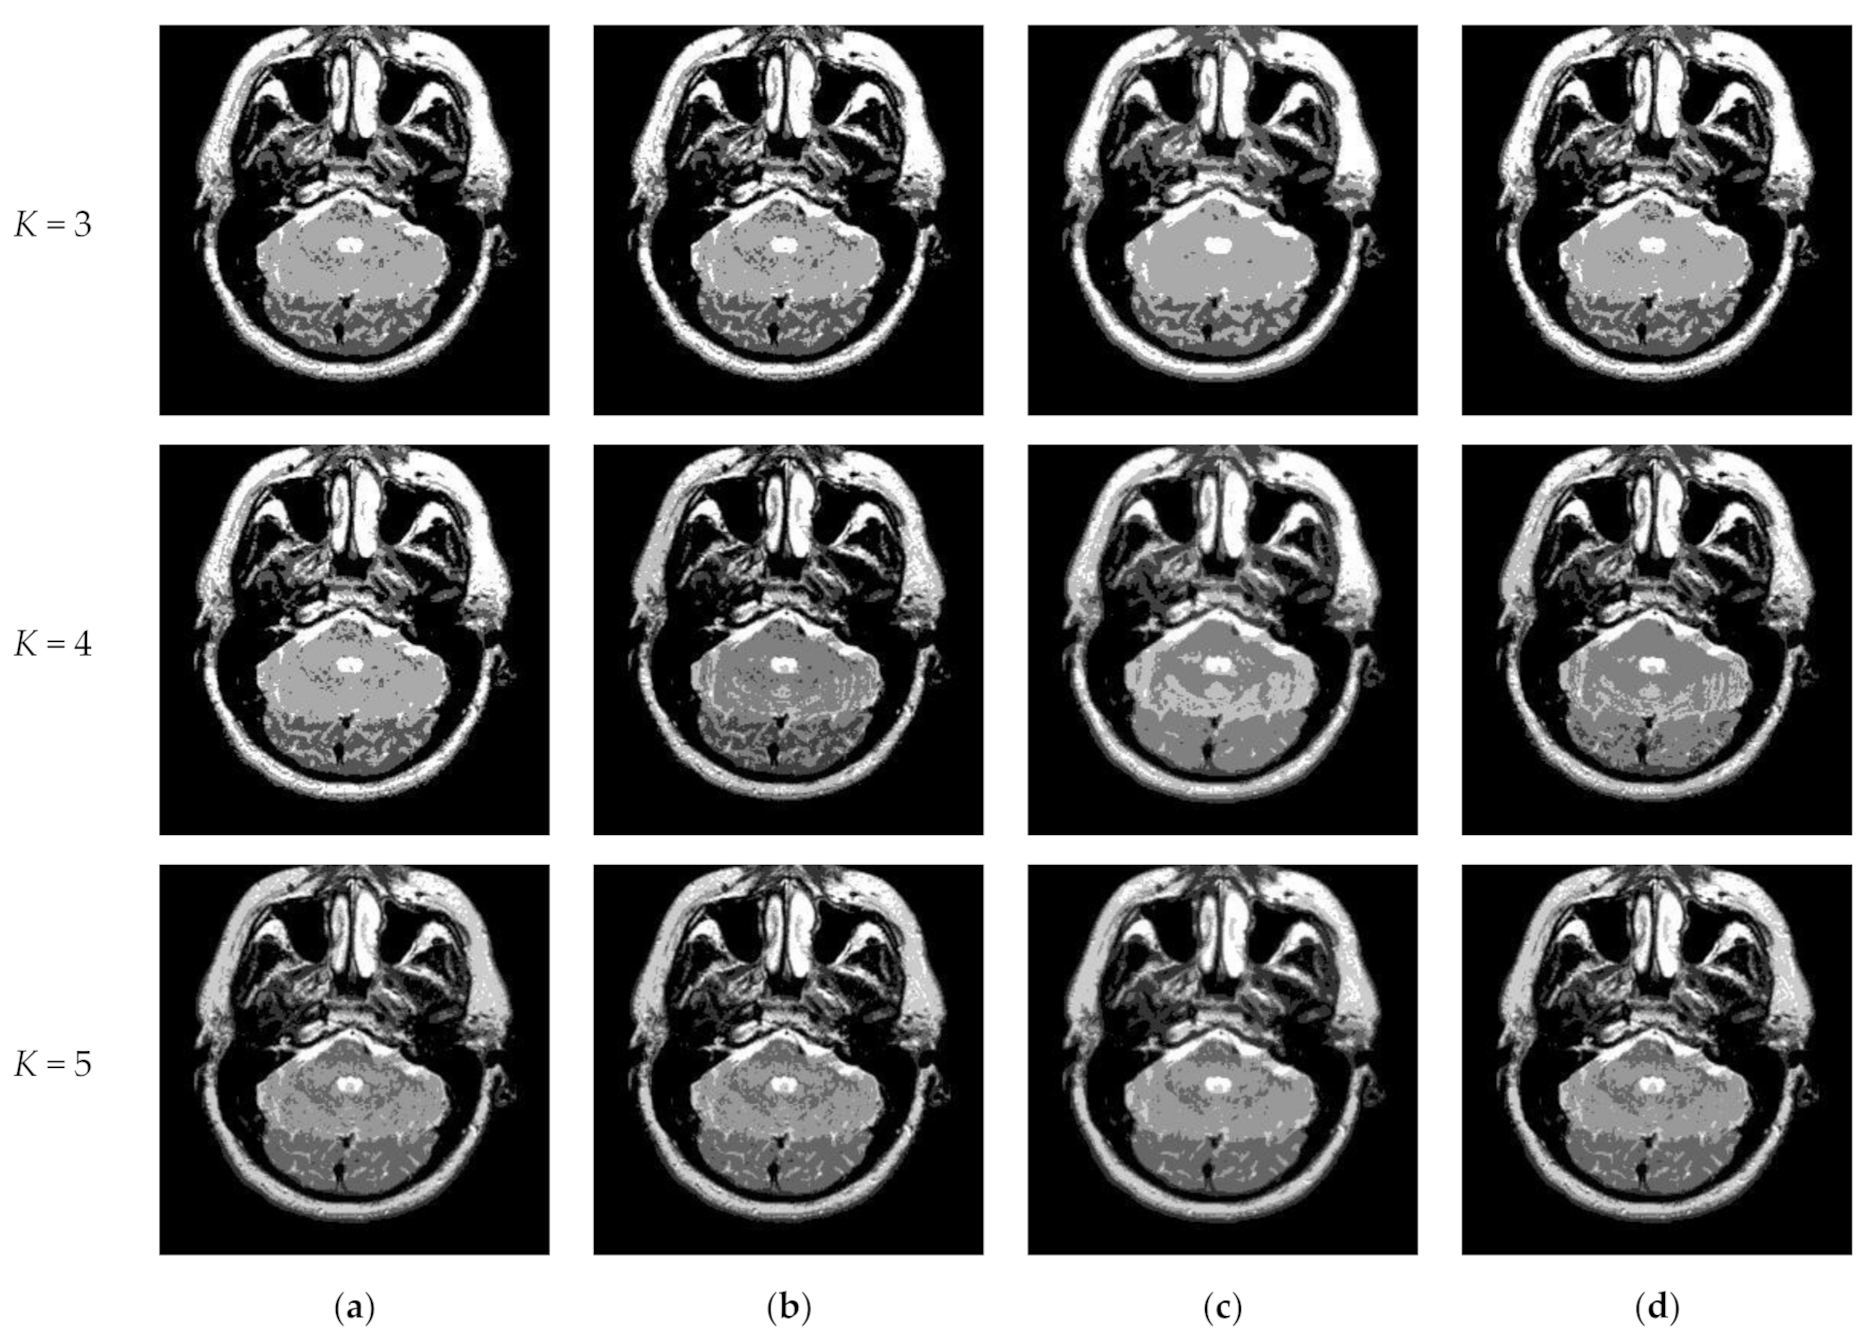

Figure 10 and Figure 11 display segmentation results of different algorithms for slice #042 and slice #082, respectively. For single level of thresholding K = 1, it can be observed that segmentation results obtained by the Otsu method have many fragmented small areas, such as the lower soft tissue in the first row of Figure 10a, whereas IIMT performs slightly better. However, the edges segmented by HL-IIMT and Proposed are much clearer. In the case of , it can be seen that Otsu and IIMT have similar segmentation effects. HL-IIMT and Proposed are better than Otsu and IIMT in terms of edge-preserving and denoising, as shown in the segmentation results in Figure 11 (K = 2, K = 4).

Figure 10.

Segmentation results obtained by different segmentation algorithms for slice #042 with number of thresholds K from 1 to 5: (a) Otsu, (b) IIMT, (c) HL-IIMT, (d) Proposed.

Figure 11.

Segmentation results obtained by different segmentation algorithms for slice #082 with number of thresholds K from 1 to 5: (a) Otsu, (b) IIMT, (c) HL-IIMT, (d) Proposed.

Table 2 shows the values of uniformity measure (U) of Proposed, HL-IIMT, IIMT, and Otsu algorithms for slice #042 and slice #082. The best evaluation results are marked in bold. It can be noted that the U values achieved by Proposed are the highest for both of the two test images. To more clearly present the results, Figure 12 illustrates the comparison of U for different algorithms based on Table 2. In Figure 12, it can be clearly noted that Proposed achieves the highest values, and HL-IIMT comes second, followed by IIMT and Otsu. This indicates that the novel thresholding method IIMT presented in this paper is effective, and our Proposed based on IIMT can obtain satisfactory segmentation results with clear edges and little noise.